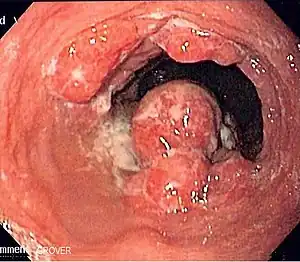

Cancers of the mouth, esophagus, pharynx, and larynx

Alcohol consumption at any quantity is a risk factor for cancers of the mouth, esophagus, pharynx and larynx. The U.S. National Cancer Institute states "Drinking alcohol increases the risk of cancers of the mouth, esophagus, pharynx, larynx, and liver in men and women, … In general, risks increases above baseline with any alcohol intake (mild; <2 glass of wine per week) and increases significantly with moderate alcohol intake (one glass of wine per day) with highest risk in those with greater than 7 glasses of wine per week. (A drink is defined as 12 ounces of regular beer, 5 ounces of wine, or 1.5 ounces of 80-proof liquor.) … Also, using alcohol with tobacco is riskier than using either one alone, because it further increases the chances of getting cancers of the mouth, throat, and esophagus."[41] The federal government's Dietary Guidelines for Americans 2010 defines moderate alcohol drinking as up to one drink per day for women and up to two drinks per day for men. Heavy alcohol drinking is defined as having more than three drinks on any day or more than seven drinks per week for women and more than four drinks on any day or more than 14 drinks per week for men.

Local carcinogenic effect of ethanol

The risk of cancer associated with alcohol consumption is higher in tissues in closest contact on ingestion of alcohol, such as the oral cavity, pharynx and esophagus. This is explained by the fact that ethanol is a proven mutagen and in addition, metabolite of ethanol (acetaldehyde) produced in the liver is highly carcinogenic, thus explaining both local (mouth, throat, esophageal cancers) as well as distant (skin, liver, breast) cancers. It is well known that ethanol causes cell death at the concentrations present in alcoholic beverages. Few cells survive a one-hour exposure to 5–10% ethanol or a 15-second exposure to 30–40% ethanol in cell culture, where surviving cells might undergo genomic changes leading to carcinogenesis. But recent evidence suggests that the cytotoxic effect of ethanol on the cells lining the oral cavity, pharynx and esophagus activates the division of the stem cells located in deeper layers of the mucosa to replace the dead cells. Every time stem cells divide, they become exposed to unavoidable errors associated with cell division (e.g., mutations arising during DNA replication and chromosomal alterations occurring during mitosis) and also become highly vulnerable to the genotoxic activity of DNA-damaging agents (e.g., acetaldehyde and tobacco carcinogens). Alcohol consumption probably increases the risk of developing cancer of the oral cavity, pharynx and esophagus by promoting the accumulation of cell divisions in the stem cells that maintain these tissues in homeostasis. Because the cytotoxic activity of ethanol is concentration-dependent, the risk of these cancers will not only increase with increasing amounts of ethanol, but also with increasing concentrations; an ounce of whisky is probably more carcinogenic when taken undiluted than when taken mixed with non-alcoholic beverages. The local cytotoxic effect of ethanol may also explain the known synergistic effect of alcohol and tobacco use on the risk of these cancers.[27]